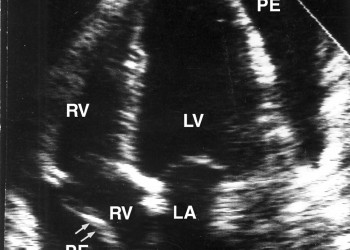

Forme particulare de pericardită

Formele particulare de pericardit? sunt cea tuberculoas?, diagnosis viral?, uremic?, neoplazic?, reumatismal?, post-infarct ?i purulent?.